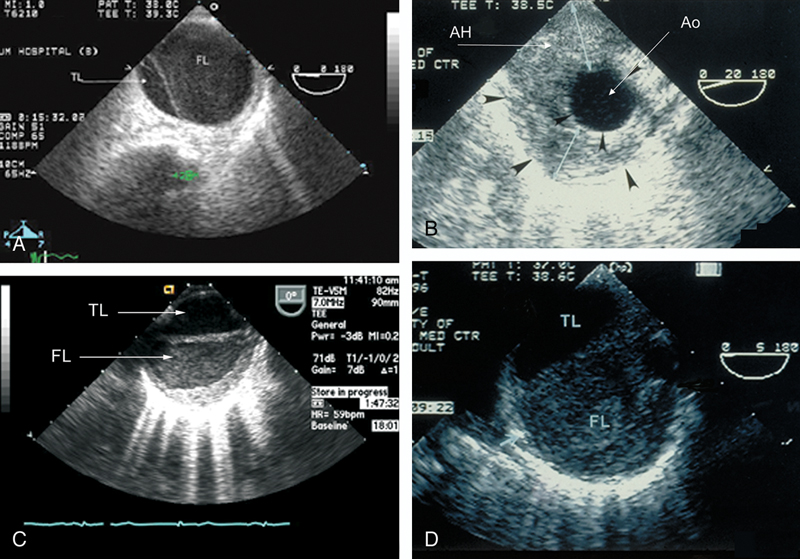

فحوصات تشخيصية لبعض امراض القلب والشرايين التاجية